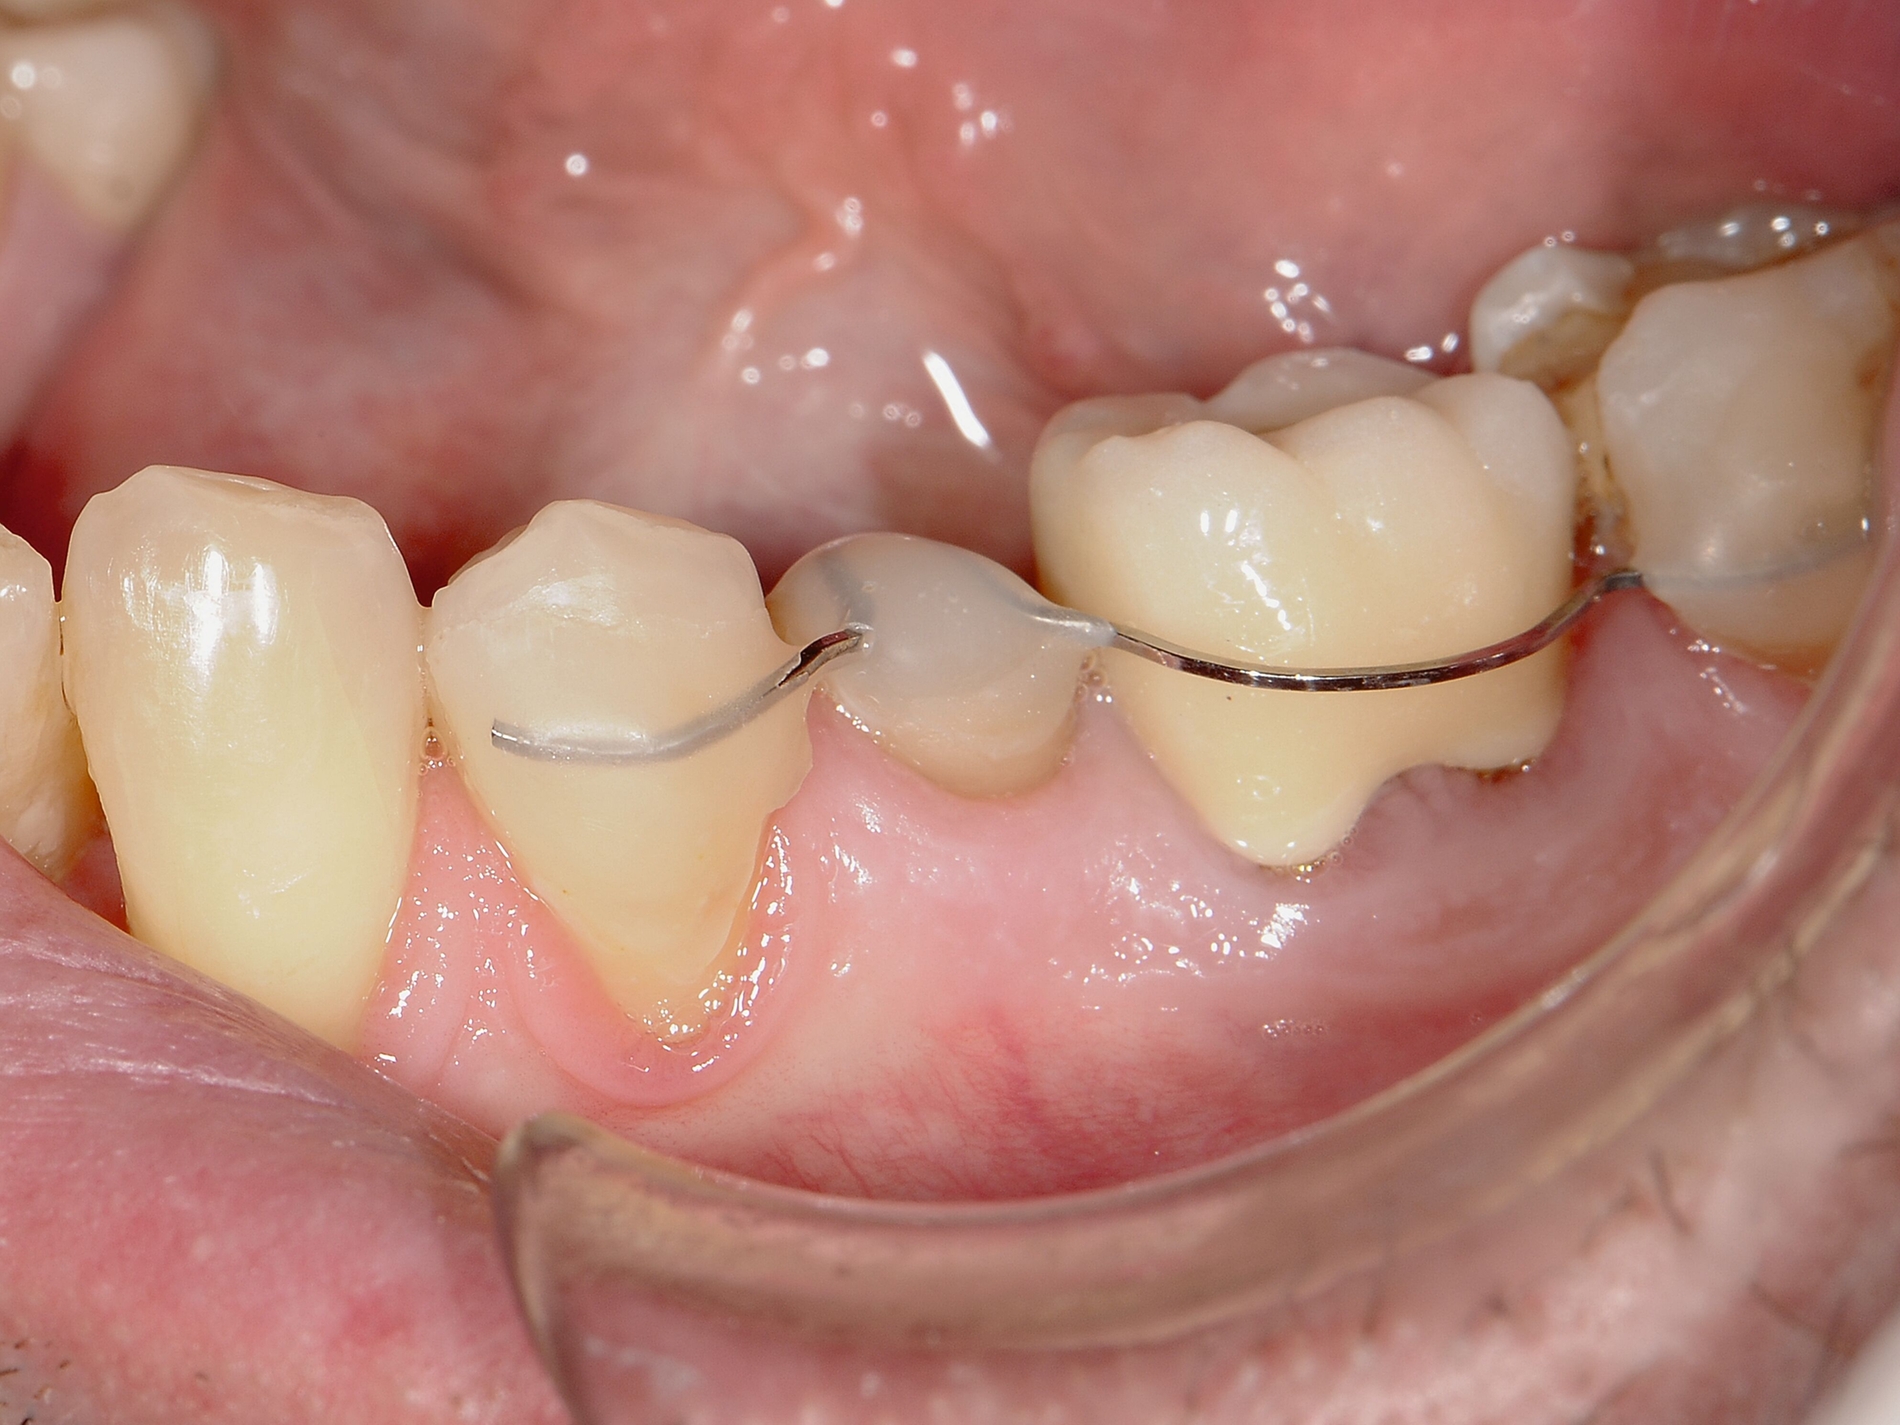

Beispielsweise kann durch eine kieferorthopädische Mesialisation nicht traumatisierter Nachbarzähne auch im wachsenden Kiefer ein traumatisch bedingtes Knochendefizit günstig beeinflusst werden [Pontoriero et al., 1987; Prapas et al., 2008; Stenvik und Zachrisson, 1993] (Abbildung 4).

Durch den Einsatz skelettaler Verankerungshilfen ist es möglich, auch in komplexeren Situationen einen kieferorthopädischen Lückenschluss durchzuführen. Mit digitalen CAD/CAM-Herstellungsmethoden wie dem selektiven Laser-Melting-Verfahren können hochindividualisierte Apparaturen angefertigt werden, die verschiedene Behandlungsaufgaben gleichzeitig adressieren beziehungsweise mit deren Hilfe Kraftvektoren präzise geplant und appliziert werden können.

Zu den weiteren Vorteilen gehören die geringeren Nebenwirkungen auf die Nachbarzähne, die bessere Planbarkeit bei Set-up-basierten Apparaturen, die gute Pflegbarkeit, die einfache Handhabung, die Verkürzung der gesamten Behandlungszeit durch reduzierte Multibracket-Phasen sowie die geringere Beeinträchtigung der orofazialen Ästhetik (Abbildung 5).